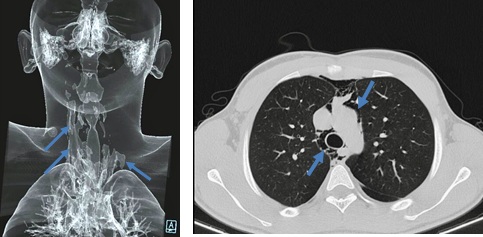

Physical examination was unremarkable, except for the presence of localised tenderness inflicted by palpation of the 2 nd and 3 rd right intercostal spaces and ipsilateral sternocleidomastoid muscle. Chest radiography revealed a right linear lucency outlining mediastinal contours, of inconclusive nature. (Figure 1) The resting electrocardiogram was normal for age. On the first day of admission, a swelling and subcutaneous emphysema were noted on the right sternal border between 2 nd/3 rd intercostal spaces. The chest ultrasound showed the presence of air bubbles in the intermuscular spaces. The Computed Tomography (CT) Scan of chest and neck confirmed the presence of air distributed bilaterally in the mediastinum, mainly on the right side and extending to the neck and dissecting the anatomical planes of the upper mediastinum. (Figure 2)

Figure 2. Patient chest computed tomography scan shows presence of interstitial air distributed bilaterally in the mediastinum, mainly on the right side and extending to the neck, and dissecting the anatomical planes of the upper mediastinum (arrows).  What is the diagnosis?